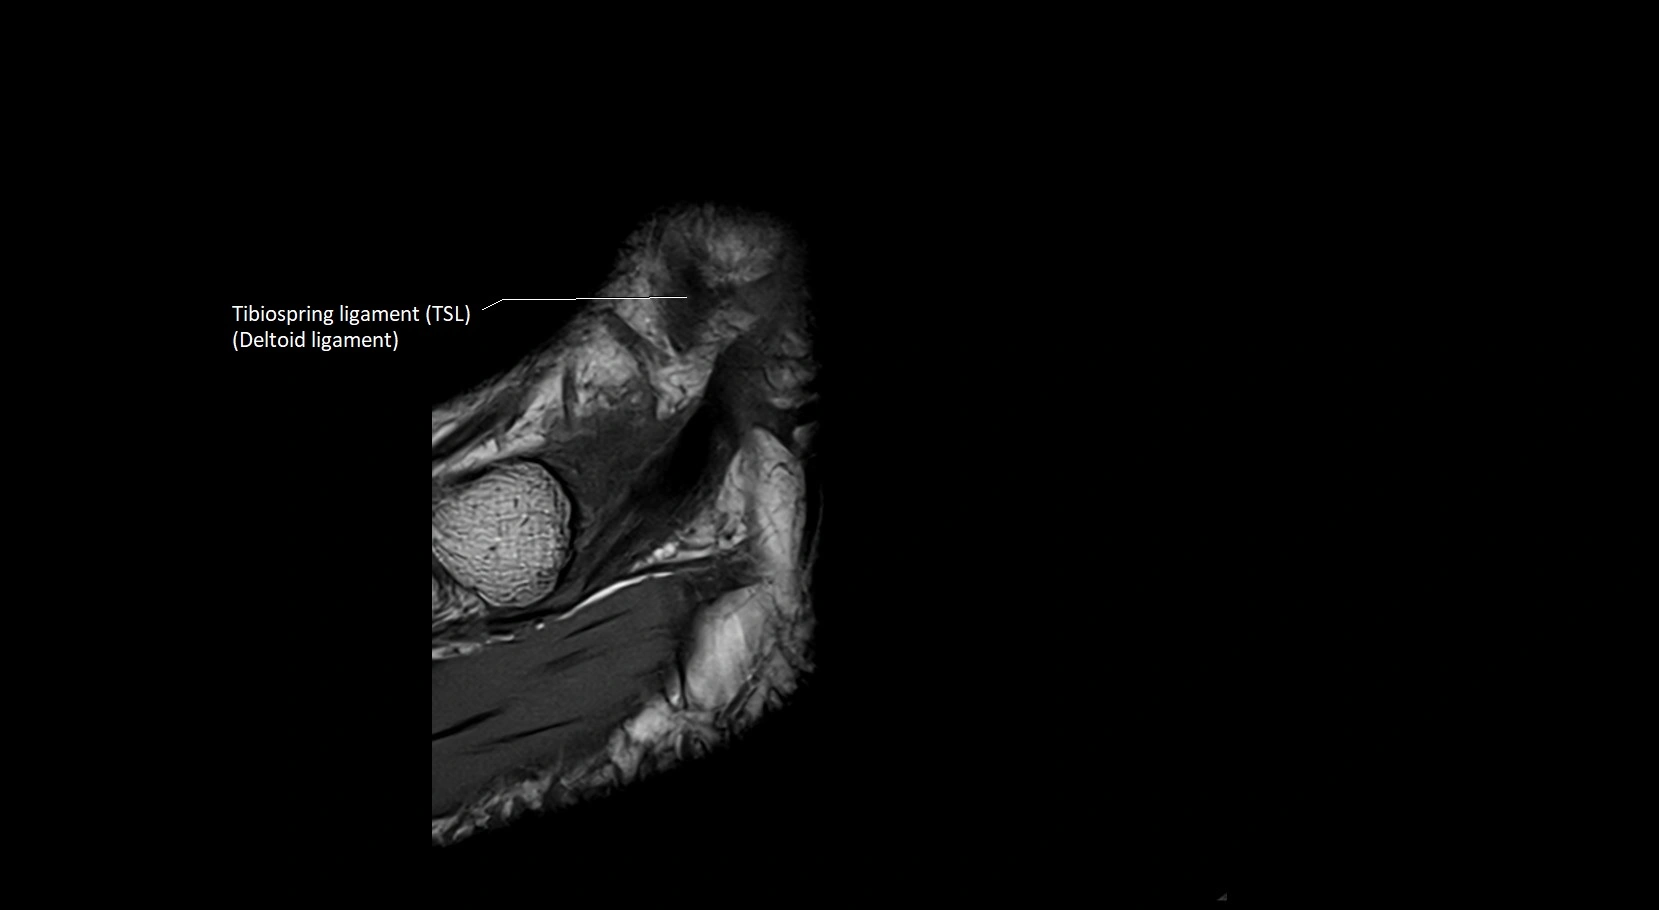

MRI image

image